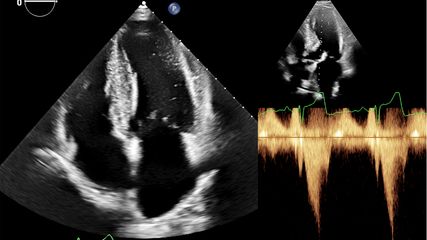

Darüber hinaus gibt die neue Guideline detaillierte Empfehlungen zu sehr speziellen Themen, wie zum Beispiel der sportmedizinischen Abklärung bei Klappenerkrankungen. Eine der zentralen Botschaften lautet hier: Asymptomatische Personen mit leichten Klappenanomalien können sich an sportlichen Aktivitäten aller Art beteiligen, während Personen mit schweren Auffälligkeiten der Herzklappen als Hochrisikopatienten gelten und intensives Training meiden sollten. Mehrere Kapitel der Leitlinie beschäftigen sich mit dem schwierigen Thema Sport und kardiale Arrhythmien.